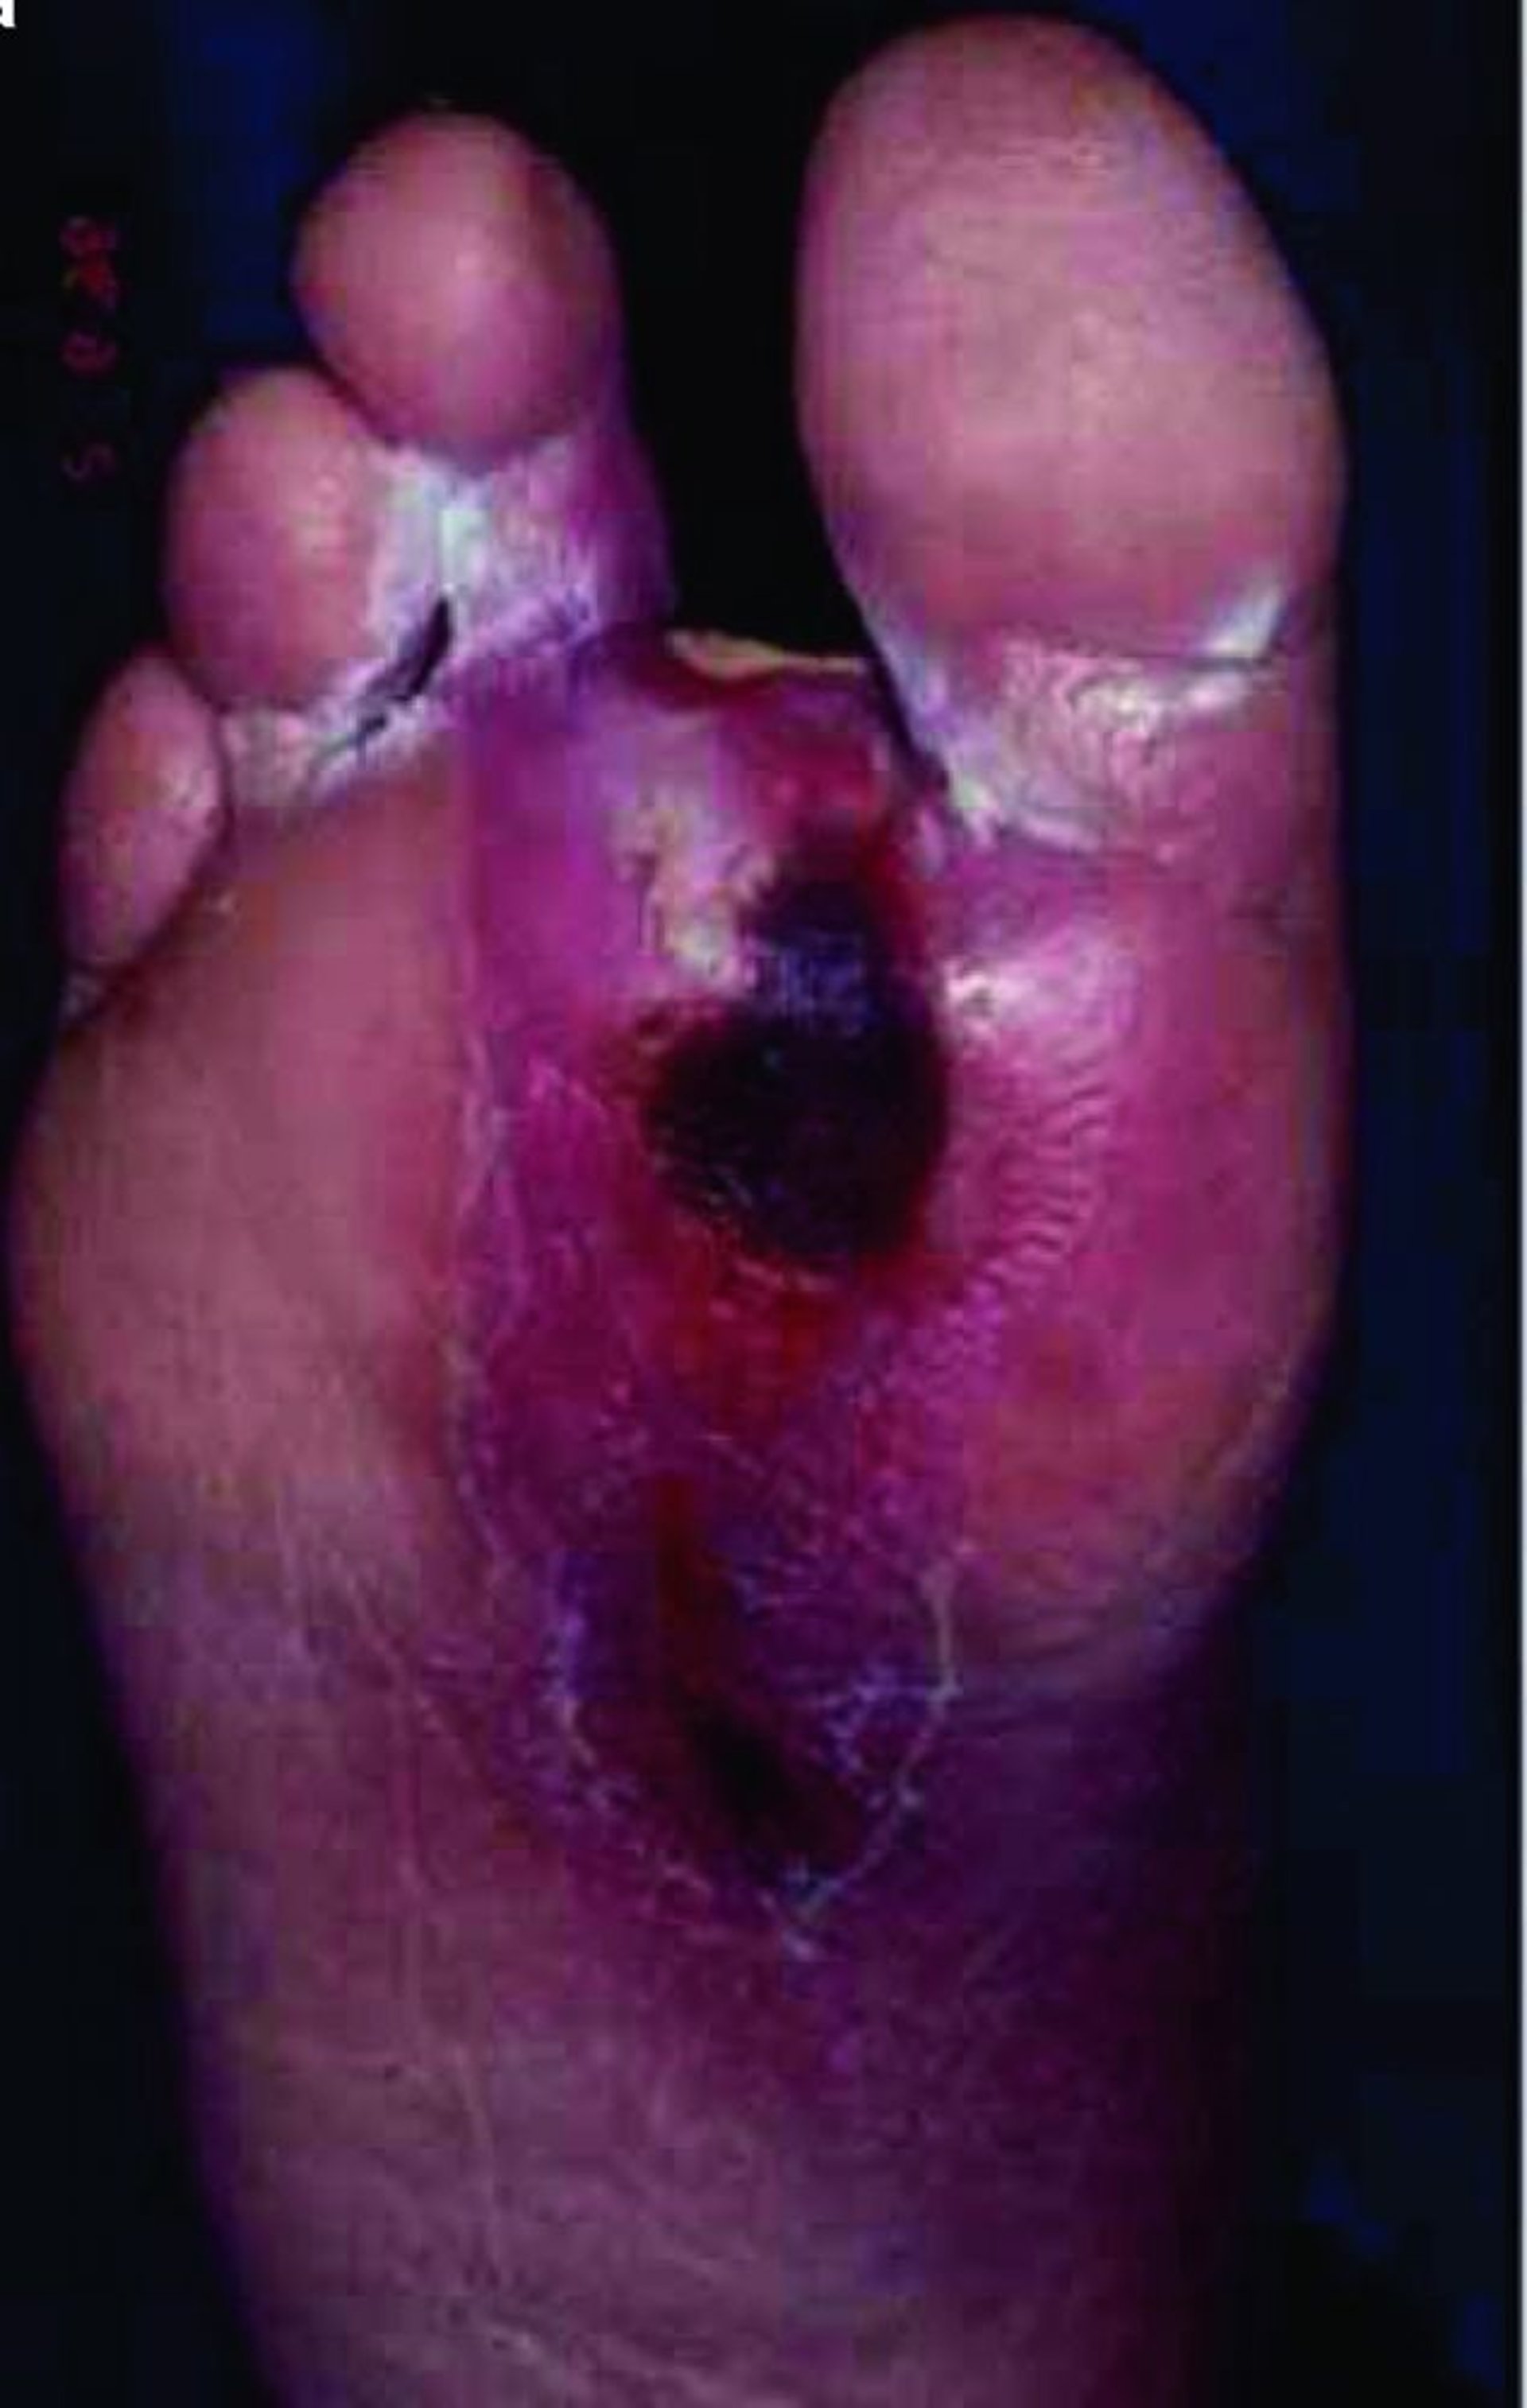

또한 당뇨병 환자들은 특히 발이나 다리에 궤양 및 감염을 갖기 쉬운데, 이는 피부로 혈액 순환이 제대로 이루어지지 않기 때문입니다. 너무나도 자주, 이러한 상처는 천천히 치유되거나 전혀 치유되지 않습니다. 상처가 치유되지 않는 경우, 감염이 되는 것이 일반적이며 이는 괴저(조직 괴사) 및 뼈 감염(골수염)을 야기할 수 있습니다. 발이나 다리 일부의 절단이 필요할 수 있습니다.

당뇨병에서의 발 문제

당뇨병은 신체에 많은 변화를 야기합니다. 발에 오는 다음의 변화들이 흔하고 치료가 어렵습니다:

• 신경에 대한 손상(신경병증)은 발의 감각에 영향을 미쳐 고통이 느껴지지 않게 합니다. 자극과 다른 형태의 손상이 감지되지 않은 채 진행될 수도 있습니다. 어떤 손상은 고통이 느껴지기 전에 피부를 통해 일어날 수 있습니다.

• 감각의 변화는 당뇨병 환자들이 그들의 발에 체중을 싣는 방식을 바꾸어 특정 지역에만 체중을 싣게 되어 굳은살을 형성합니다. 굳은살(그리고 건성 피부)은 피부가 무너질 위험을 증가시킵니다.

• 당뇨병은 발의 순환을 어렵게 하여 피부가 손상되었을 때 궤양 형성 가능성을 높이고 궤양의 치유를 늦춥니다.

당뇨병이 신체가 감염에 대항하는 능력에 영향을 미칠 수 있기 때문에 발 궤양이 일단 형성되면 쉽게 감염이 됩니다. 신경병성 때문에 사람들은 감염이 심각해지고 치유가 어려워지고 괴저 형성이 될 때까지 감염에 의한 불편함을 느끼지 못할 수도 있습니다. 당뇨병 환자들은 당뇨병을 갖지 않는 사람들보다 발이나 다리를 절단할 가능성이 30배 이상 많습니다.

발 관리가 매우 중요합니다(발 관리 참조). 발은 감염으로부터 보호되어야만 하고, 피부는 좋은 보습제로 항상 촉촉하게 유지해야 합니다. 적당히 잘 맞는 신발을 신고, 자극을 주는 부위가 없어야 합니다. 신발에는 서 있을 때 압력을 분산시키기 위한 적합한 쿠션이 있어야 합니다. 맨발로 다녀서는 안됩니다. 또한, 발톱 깎거나 굳은살 제거와 같은 발병 전문가(발 관리를 전문으로 하는 의사)로부터의 정기적인 관리가 도움이 될 수도 있습니다. 또한, 발에 대한 감각과 혈류는 정기적으로 의사에게 평가받아야만 합니다.